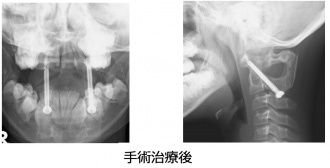

環軸椎亜脱臼

環椎(第1頚椎)と軸椎(第2頚椎)の不安定性が強いため亜脱臼をきたしているもので、 放置すると頸髄損傷をきたして手足が動かなくなってしまう可能性のある疾患です。全身の関節が柔らかいダウン症候群の患者さんに多く、重症例には手術が必要になります。